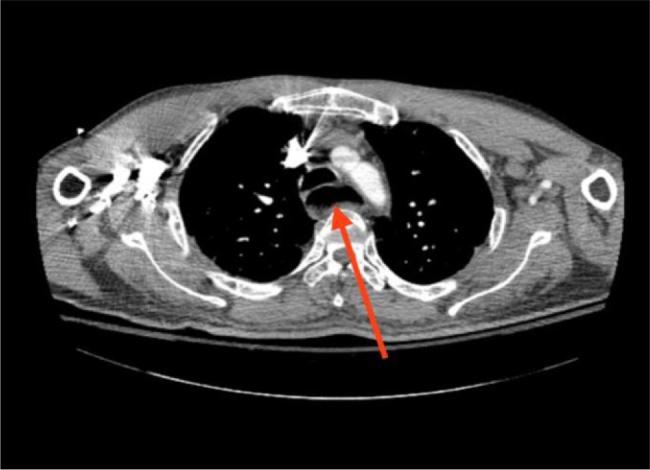

夏科-马里-图斯病患者的食管动力障碍:病例报告及文献综述

Oesophageal Dysmotility in a Patient with Charcot-Marie-Tooth Disease: Report and Literature Review.

Oesophageal dysmotility is a serious condition characterised by impaired coordination of oesophageal smooth muscle contractions, which can be secondary to a variety of causes including infection, inflammation and malignancy. The presenting symptoms are variable and include chest or epigastric pain, food regurgitation, heartburn or cough, making it difficult to distinguish. Diagnostic modalities and treatment strategies vary depending on the underlying cause. Once oesophageal dysmotility is suspected, a thorough evaluation is essential as the management strategies and prognosis of the condition differ significantly based on the underlying pathology. A multidisciplinary approach and clinical expertise are essential for optimal patient care and treatment. While neuromuscular disorders are associated with swallowing dysfunction due to oropharyngeal muscle involvement, oesophageal smooth muscles involvement is rare. This case highlights the importance of careful and frequent evaluation of both respiratory and gastrointestinal smooth muscle function, particularly in patients with chronic neurological disorders.

食管动力障碍是一种严重疾病,其特征为食管平滑肌收缩协调受损,可能继发于多种原因,包括感染、炎症和恶性肿瘤。临床表现多样,包括胸痛或上腹痛、食物反流、烧心或咳嗽,难以鉴别。诊断方法和治疗策略因潜在病因而异。一旦怀疑有食管动力障碍,进行全面评估至关重要,因为基于潜在病理情况,该病的管理策略和预后差异很大。多学科方法和临床专业知识对于优化患者护理和治疗至关重要。虽然神经肌肉疾病因口咽肌肉受累而与吞咽功能障碍相关,但食管平滑肌受累罕见。本病例强调了仔细且频繁评估呼吸和胃肠道平滑肌功能的重要性,尤其是在慢性神经疾病患者中。